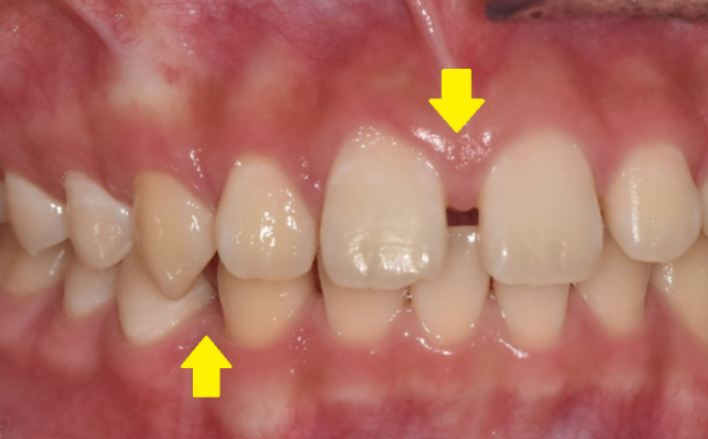

가운데 치아가 눈에 띄게 벌어져있는 환자분

앞니끼리 벌어진 공간이 좁을 경우는

| 1. 앞니만 벌어졌을 경우는 “부분 교정” |

| 3. 치아 크기가 작은 경우 ” 교정과 보철 치료 동시에 “ |